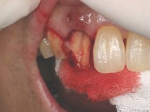

抜歯を行う。折れていた位置がかなり深い位置であるのがわかる。

歯根も抜歯

抜歯した穴をよく掃除(掻爬)後すぐにインプラントを埋入